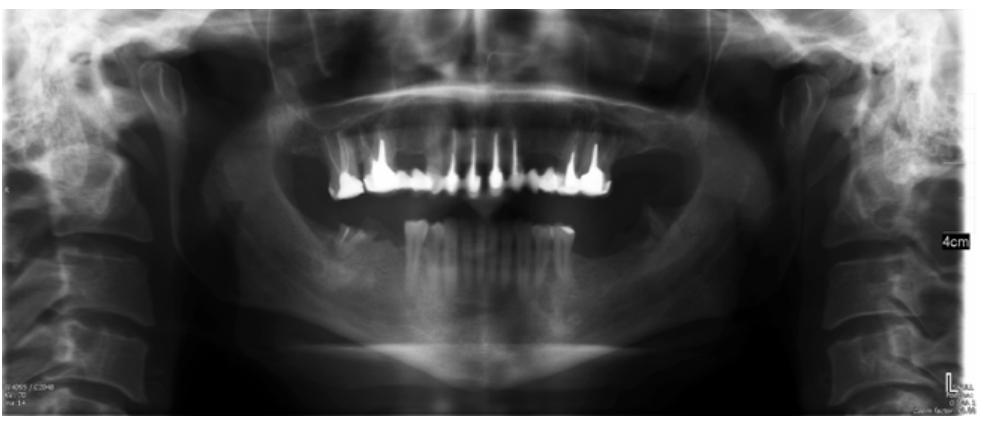

Técnica combinada de microabrasión y blanqueamiento dental para tratamiento de pigmentaciones asociadas a fluorosis. Reporte de un caso

La fluorosis dental es una condición irreversible originada durante el desarrollo dental que genera pigmentaciones intrínsecas, alteraciones en el esmalte manifestadas a manera de manchas blancas, amarillas o marrones, que perjudican la estética y repercuten en el desenvolvimiento social. El presente reporte de caso clínico describe la combinación de los procedimientos de microabrasión y blanqueamiento dental, como alternativas en la eliminación de pigmentaciones dentales. Después del diagnóstico de la patología, verificación de ausencia de lesiones pulpares y caries, una explicación minuciosa a la paciente y obtención del consentimiento informado, se realizó limpieza de las superficies dentales y, bajo aislamiento absoluto, se procedió a realizar la técnica de microabrasión mediante ácido clorhídrico al 6,6% siguiendo las instrucciones del fabricante. Concluido el procedimiento y, observando que era posible mejorar aún más la estética, se decidió ejecutar el procedimiento de blanqueamiento dental, a base de peróxido de hidrógeno al 40% en el consultorio, seguido por peróxido de carbamida al 10% aplicado en el domicilio. Al finalizar el tratamiento se observó uniformidad en el color dental, conjugados con una evidente mejora en la calidad de vida y relación social de la paciente.